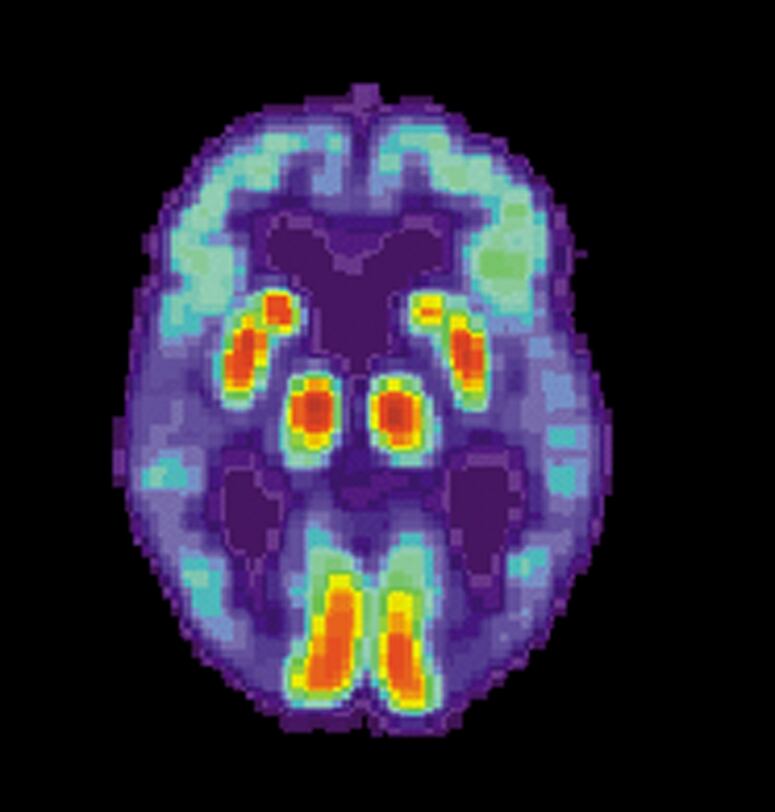

¿Cómo lo supieron? La investigadora Daniela Perani y su equipo realizaron escáneres cerebrales y pruebas de memoria a 85 personas mayores de 65 años, todas con alzhéimer. Entre los participantes, 45 hablaban tanto alemán como italiano y 40 solamente hablaban un idioma.

¿A qué se debe? El estudio, publicado en la revista Proceedings of the Natural Academy of Sciences (PNAS) estima que las personas bilingües parecieron tener una mejor conectividad funcional en las regiones frontales del cerebro, lo que les permitía mantener un mejor pensamiento, mejor memoria y mejores funciones básicas a pesar del alzhéimer.